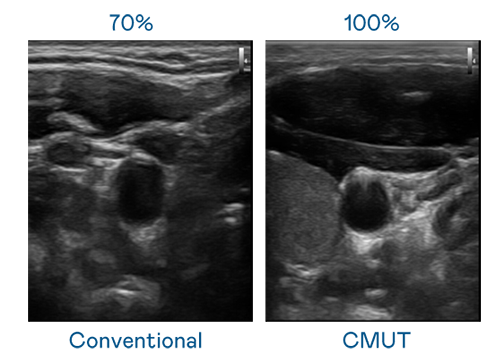

CMUT 技术是一种用电容式微机电元件来产生超音波讯号的技术。与传统 PZT 压电式技术相比,CMUT 频宽增加 30%,更宽频的超音波讯号让影像解析度大幅提升,是实现高影像品质医疗超音波扫描、促进精准医疗发展的关键技术。

大频宽带来超清晰影像

超音波影像的解析度高低,首先取决于探头能发出的讯号频宽。朋友的闺蜜2线观高清电视 CMUT 可提供高清晰的超音波讯号,提供高频宽、高灵敏度、影像纹理细节更高的超音波影像,协助医护人员缩短影像判读时间及利用精准的医疗影像进行诊断。